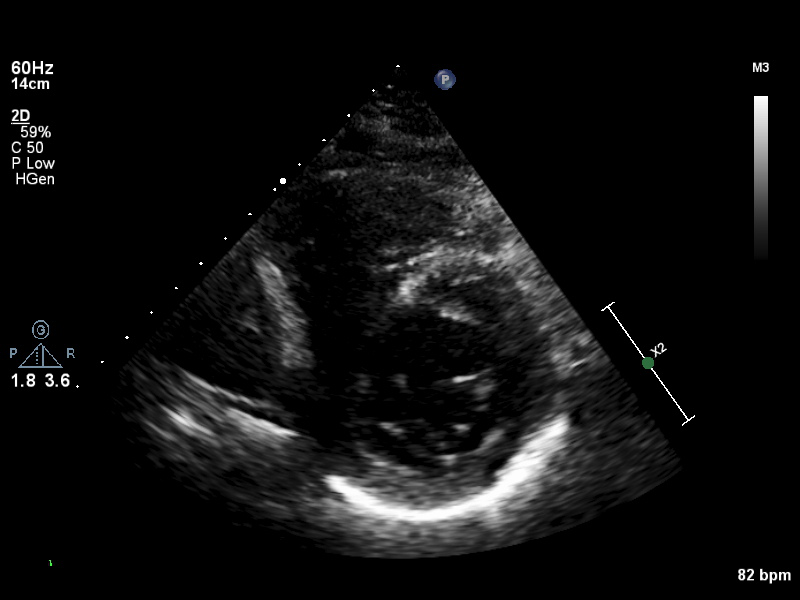

PSAX (7 views)

ImageView NameDescription

psax-all psax-all Valve level, field of view covers TV/AV/PV positions

psax-tv psax-tv Focused on tricuspid valve

psax-av psax-av Focused on aortic valve

psax-pv psax-pv Focused on pulmonary valve

psax-lv-base psax-lv-base Left ventricle base level

psax-lv-mid psax-lv-mid Left ventricle mid level

psax-lv-apex psax-lv-apex Left ventricle apex level